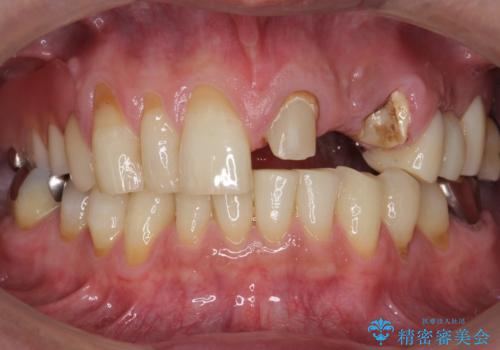

- ブリッジの支台歯であった左上の犬歯が折れたことを主訴に来院された患者様です。

犬歯は歯ぐきの奥深くまで割れており保存不可能な状態でしたが、どうしても抜きたくないとのことでした。

歯の牽引後、ブリッジの仮歯で保定しながら歯肉・骨の治癒を待ったのち、ブリッジによる補綴を行いました。

根の長さが短くなるためブリッジの支台歯としては弱いこと、長期的予後は不明なことをご理解頂いた上で治療を行いました。

根管治療はご希望されず行っておりません。

左上2欠損部の軟組織のボリュームが少なくポンティック部に食渣がたまりやすい歯肉形態であったため、歯槽堤増大術も提案しましたがご希望されませんでした。